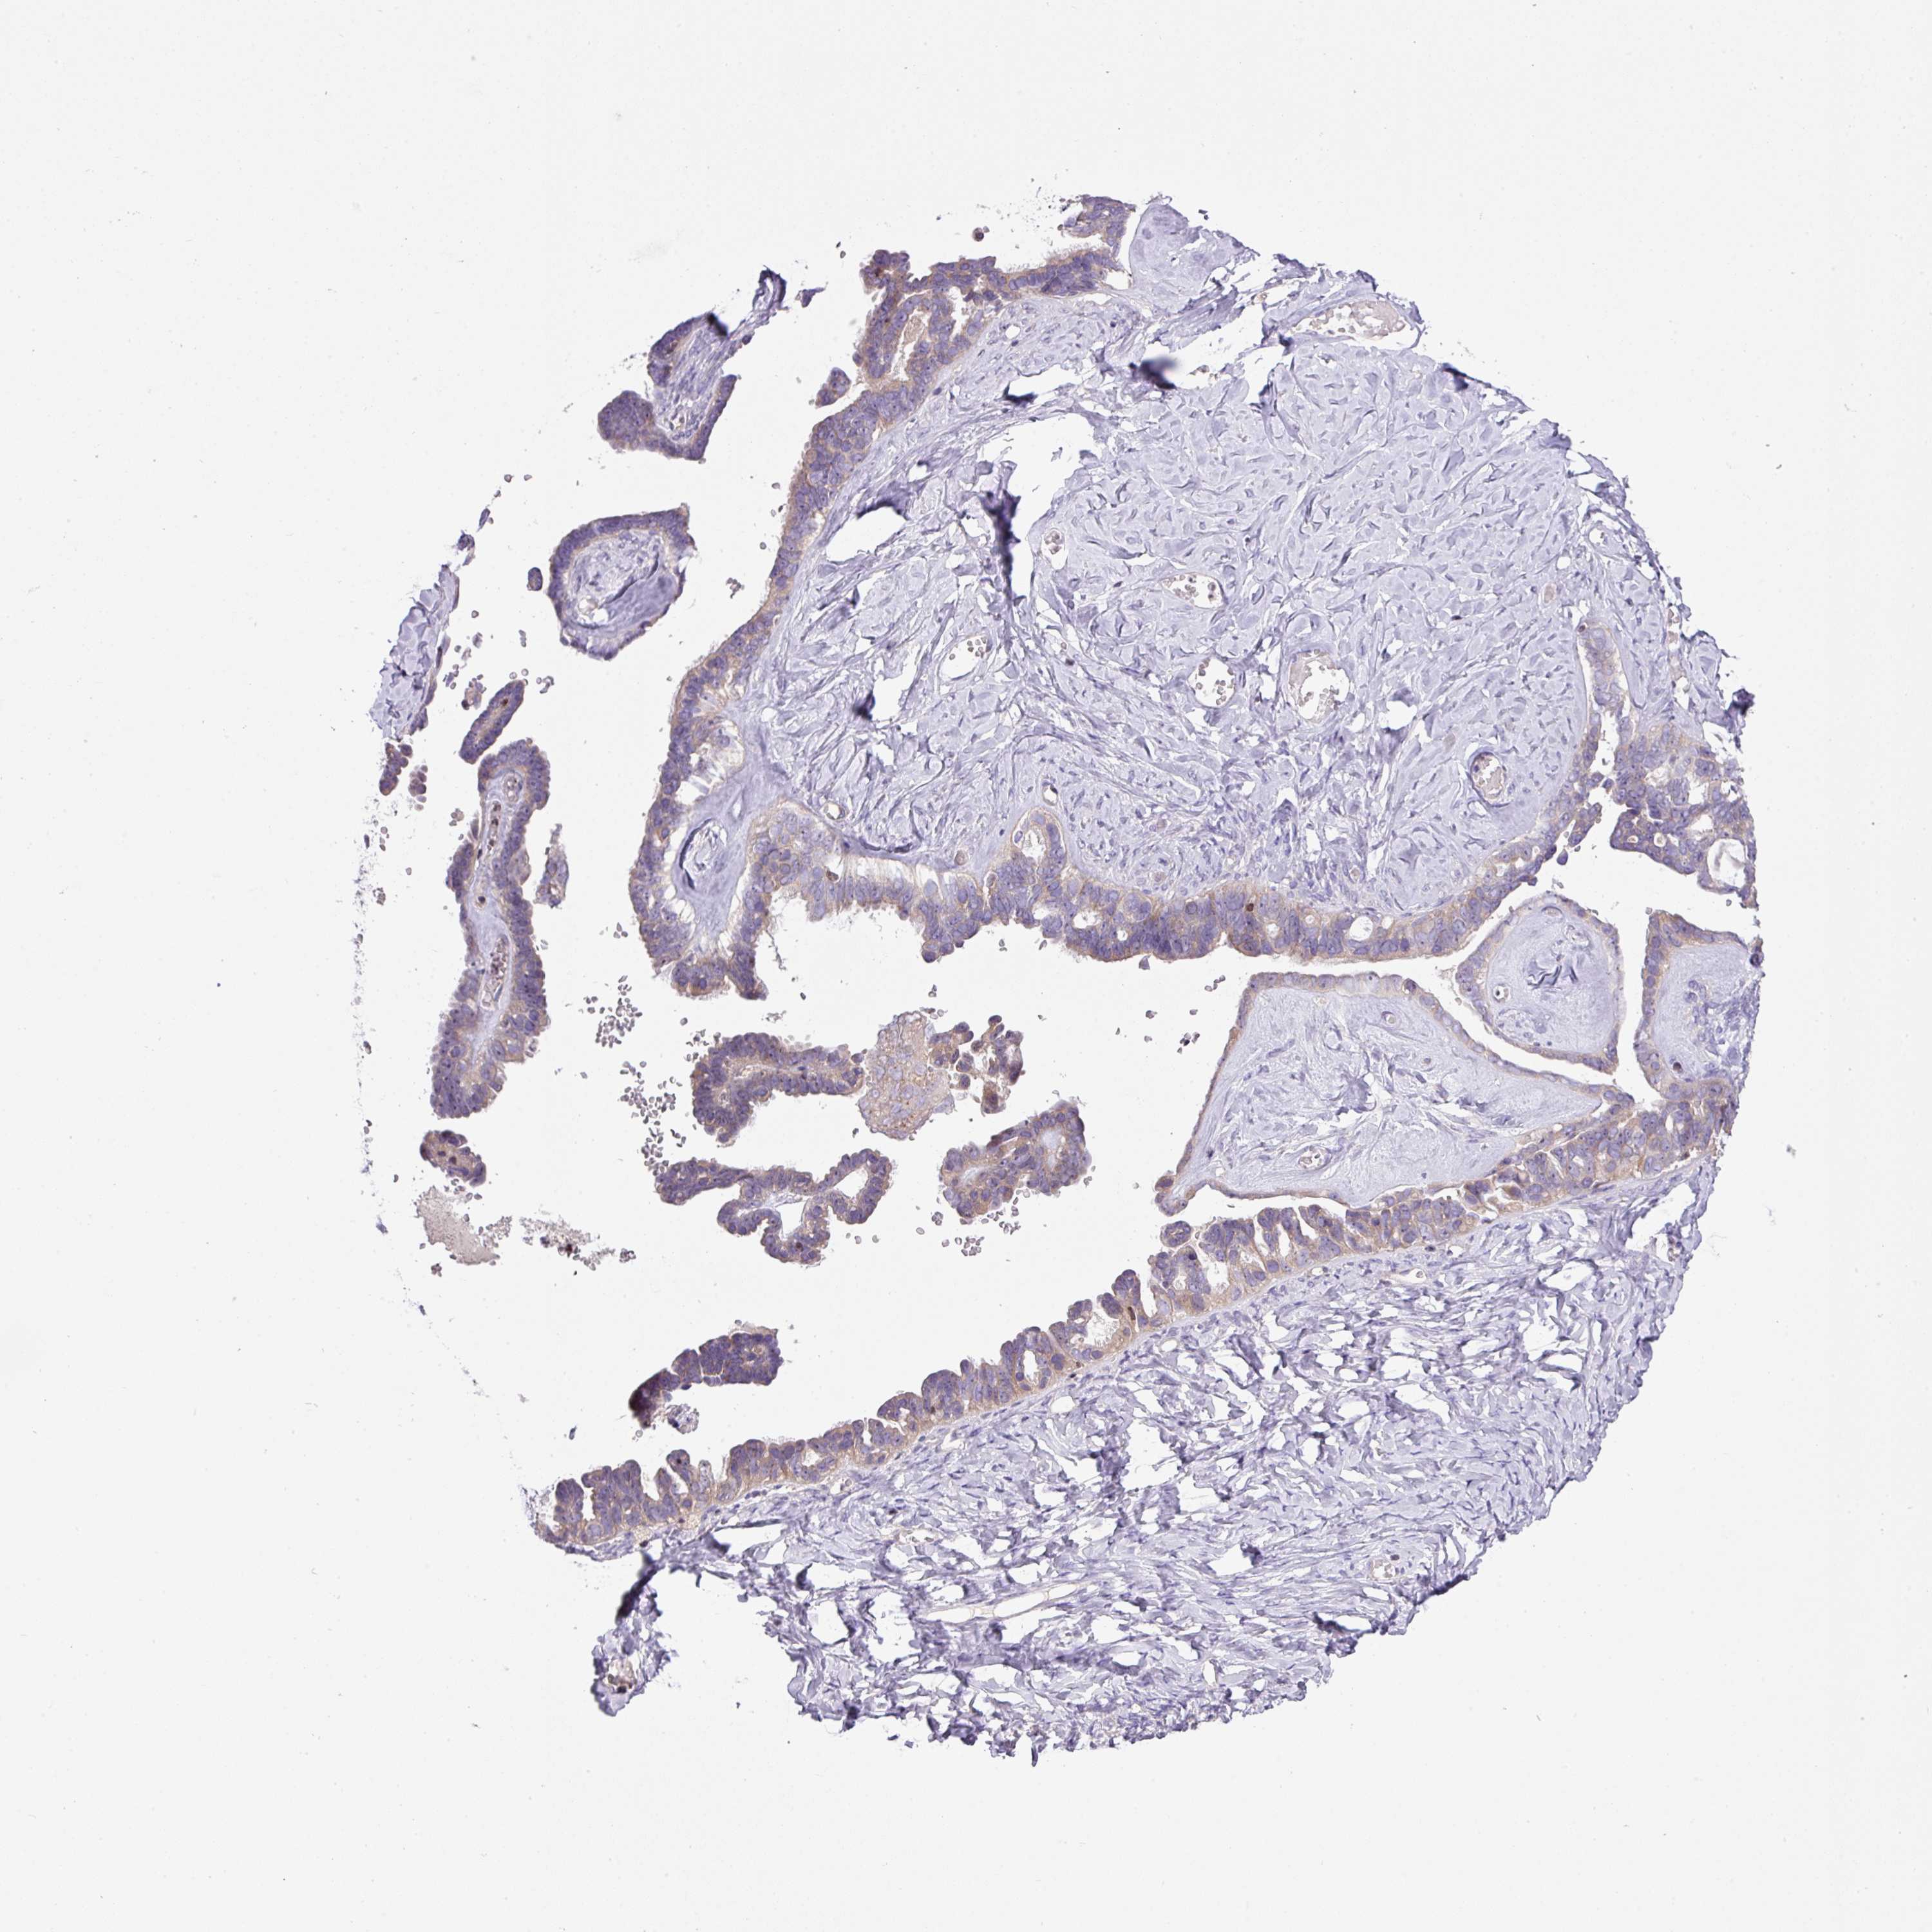

OVARIAN CANCER - Protein expressioni

A mouse-over function shows sample information and annotation data. Click on an image to view it in a full screen mode. Samples can be filtered based on level of antibody staining by selecting one or several of the following categories: high, medium, low and not detected. The assay and annotation is described here.

Note that samples used for immunohistochemistry by the Human Protein Atlas do not correspond to samples in the TCGA dataset.

Antibody stainingi

Antibody staining in the annotated cell types in the current human tissue is reported as not detected, low, medium, or high, based on conventional immunohistochemistry profiling in selected tissues. This score is based on the combination of the staining intensity and fraction of stained cells.

Each image is clickable and will lead to virtual microscopy that enables deeper exploration of all samples and also displays staining intensity scores, fraction scores and subcellular localization as well as patient and tissue information for each sample.

Antibody HPA051421

Antibody HPA054639

Cystadenocarcinoma, serous, NOS

Cystadenocarcinoma, mucinous, NOS

Adenocarcinoma, NOS

Carcinoma, endometroid